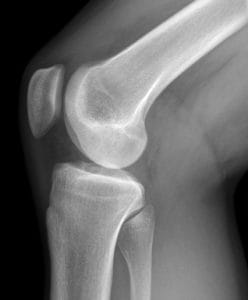

Knee Cracking: Noisy Knees are No Worry

Knee cracking, popping and creaking are very common complaints but are actually nothing to worry about. Today’s post is an explanation of what causes the cracking in your knees, why it is no issue and what you can do to help it if it still gives you or a family member the heebie-jeebies…

knee cracking - what causes itWhat causes knee cracking?